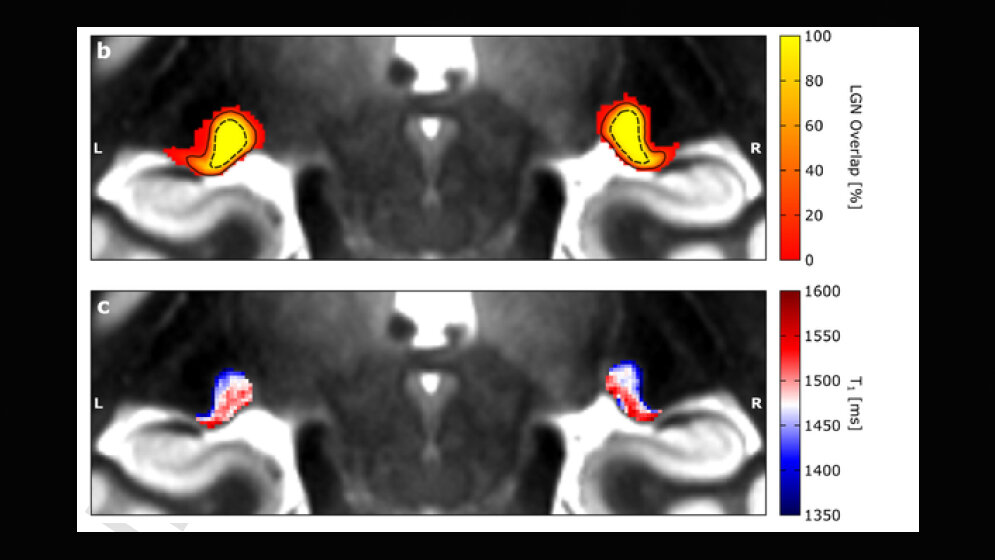

Diese Schwierigkeit, den visuell-sensorischen Thalamus im Detail zu untersuchen, hat das Verständnis über die Funktionsweise der visuellen Sinnesverarbeitung in der Vergangenheit stark beeinträchtigt. Christa-Müller Axt ist Doktorandin und beschäftigt sich in der Abteilung von Neurowissenschaftlerin Prof. Katharina von Kriegstein an der TU Dresden mit dem visuell-sensorischen Thalamus. Durch Zufall entdeckte die Doktorandin in Neuroimaging-Daten Strukturen, die den beiden visuell-sensorischen Thalamus-Teilen ähnelten. Die Neuroimaging-Daten waren einzigartig, da sie eine äußerst hohe räumliche Auflösung aufwiesen und mit einem speziellen Magnetresonanztomografen (MRT) am MPI-CBS in Leipzig aufgenommen wurden, wo von Kriegsteins Gruppe neurowissenschaftliche Studien zu Legasthenie durchführte. Christa Müller-Axt verfolgte diese Entdeckung in einer Reihe weiterer neuartiger Experimente, bei denen sie in-vivo- und post-mortem-MRT-Daten mit hoher räumlicher Auflösung sowie post-mortem Histologie analysierte, und war sich bald sicher, die beiden Teile des visuell-sensorischen Thalamus entdeckt zu haben. Die hochauflösenden strukturellen qMRT-Daten wurden auf einem 7 Tesla Magnetom MRT-System (Siemens Healthineers, Erlangen, Deutschland) unter Verwendung einer 24-Kanal-Kopfspule (NOVA Medical, Wilmington MA, USA) aufgenommen. Jede Hemisphäre wurde separat mit einer 3D-MP2RAGE-Sequenz abgebildet.

Die Ergebnisse zeigen, dass die zwei Teile des visuell-sensorischen Thalamus durch unterschiedliche Mengen an weißer Hirnsubstanz (Myelin) gekennzeichnet sind. Diese Information lasse sich in den neuartigen MRT-Daten erkennen und könne somit zur detaillierten Untersuchung des visuell-sensorischen Thalamus beim lebenden Menschen verwendet werden. „Die Erkenntnis, dass wir die Teile des visuell-sensorischen Thalamus bei lebenden Menschen darstellen können, ist fantastisch. In naher Zukunft kann man damit die visuell-sensorische Verarbeitung sowohl bei gesunden, als auch bei kranken Menschen untersuchen“, sagt Erstautorin Christa Müller-Axt und erklärt: „Post-mortem Studien bei Legasthenie haben gezeigt, dass es speziell in einem der beiden Teile des visuell-sensorischen Thalamus strukturelle Veränderungen gibt. Jedoch gibt es nur sehr wenige dieser post-mortem Untersuchungen, weswegen es schwierig zu sagen ist, ob alle Legastheniker diese Art von Veränderungen im visuell-sensorischen Thalamus aufweisen. Außerdem können post-mortem Daten nichts über die funktionellen Auswirkungen dieser Veränderungen und ihren spezifischen Beitrag zu den Entwicklungssymptomen der Legasthenie aussagen. Daher erwarten wir, dass unser neuartiger in-vivo Ansatz die Forschung über die Rolle des visuell-sensorischen Thalamus bei Legasthenie erheblich erleichtern und vorantreiben wird.“